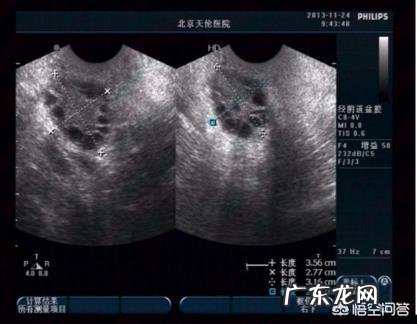

黄医生在评估多囊卵巢怀孕几率的时候 , 往往是依据“排卵次数”来预估的 。这个时候大家会反驳黄医生:多囊都已经不排卵了 , 为什么能这样算?

准确地讲多囊卵巢的排卵特征是“稀发排卵”或者是“偶发排卵” , 多囊粉丝哪怕一年只有一次排卵的机会还是有成功怀孕的几率的 。